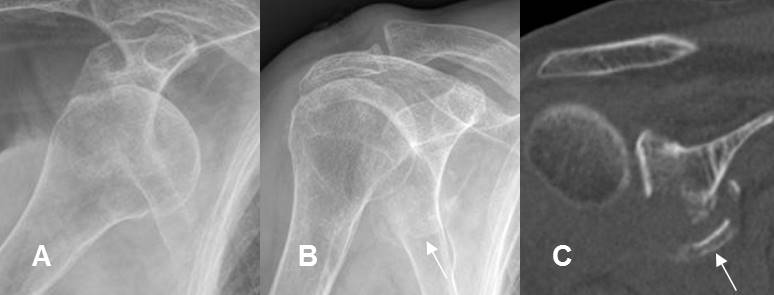

Fig 162. Luxofractura.

A: Rx AP. Luxación anterior del hombro.

B: Rx AP. Después de la reducción, se identifican fragmentos óseos sueltos en la parte inferior de la glenoides.

C: TAC reconstrucción coronal. Se confirma la luxofractura, con fractura desplazada y conminuta de la glenoides inferior.